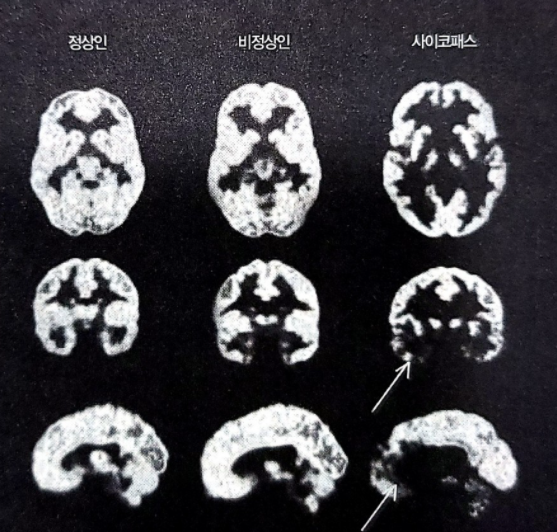

<사이코패스 뇌과학자>의 저자는 뇌과학자이다. 그는 사이코 패스를 연구하는 사람이며, 무엇보다 그 자신이 '사이코패스적인 뇌'를 가지고 있다. 물론 그도 처음엔 자신이 그런 뇌를 가지고 있는 줄 몰랐다. 그는 자신의 가족 뇌 스캔 사진을 살펴보다 어떤 사진을 보게 된다. 안와피질, 복측피질, 측두피질 뿐 아니라 연결 조직까지 전형적인 사이코패스의 특성이 드러난 사진이었다. 저자는 자신의 눈을 믿을 수 없었다.

사이코 패스의 뇌는 몇몇 특징이 있다. 안와,즉 눈의 윗부분복내측전전두피질에서 활동이 저조하다. 이들 부위는 억제, 윤리, 도덕성에 관여한다고 알려져 있다. 또한 보통 사이코패스라면 측두엽의 앞쪽에도 손상이 있다. 감정을 처리하는 편도체가 거기 있어서, 그곳이 손상되면 결국 냉정하게 행동하게 된다. 그리고 마지막으로 뇌섬엽 역시 활동 저하를 보인다. 이는 공감 능력 저하로 이어진다.

충동적인 사람들은 흔히 안와피질이 제대로 작동하지 않고 성욕이 과다하며, 쉽게 욱하는 사람들은 흔히 편도체의 기능 문제가 있다. 대상피질 기능에 문제가 있으면 기분을 조절하고 행동을 제어하는 데 문제가 생긴다. 하지만 보통 일반적인 살인마들은 이 중 한두 개의 문제만 보인다. 하지만 변연피질, 전전두피질, 측두피질 복합체 전체에 걸쳐 기능이 저하되는 패턴은 사이코패스의 뇌가 유일한 것처럼 보인다.